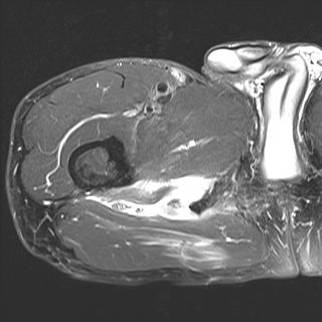

MRI

Complete / retracted tears

Proximal hamstring tear on right (red circle), normal insertion on tuberosity on left (blue circle)

Proximal hamstring avulsion on right - red circle is retracted hamstring tendon, blue circle is normal insertion on left

Proximal hamstring tear on right (red circle), normal insertion on left (blue circle)

Proximal hamstring avulsion, with tendon floating in hematoma / seroma